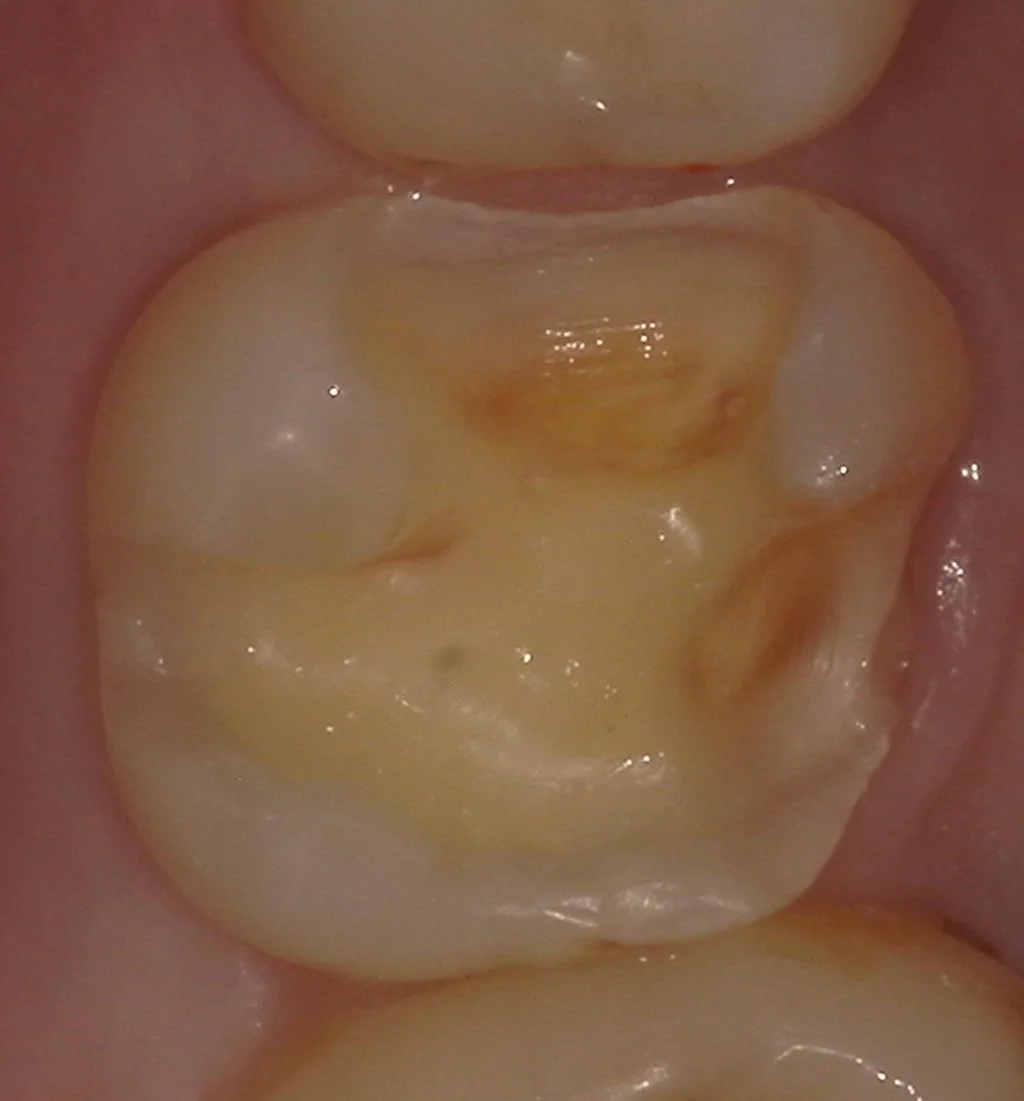

さて、金属を外して虫歯を取ったのがこちらです。

まずは嚙む面からの写真です。

歯の一部に着色が残っているのが分かるかと思いますが、この部位は虫歯が深すぎて、着色部分を除去すると神経が出てしまう危険性があった場所になります。

色自体は残っていますが、虫歯は残っていません。

本来であれば接着の面から言えば全て除去することの方が望ましいですが、そのせいで神経が出てしまうと本末転倒なので、私は深い部分の着色は無理に除去せずに残していることが多いです。

非常に内面の深くにまで虫歯が入り込んでいました。